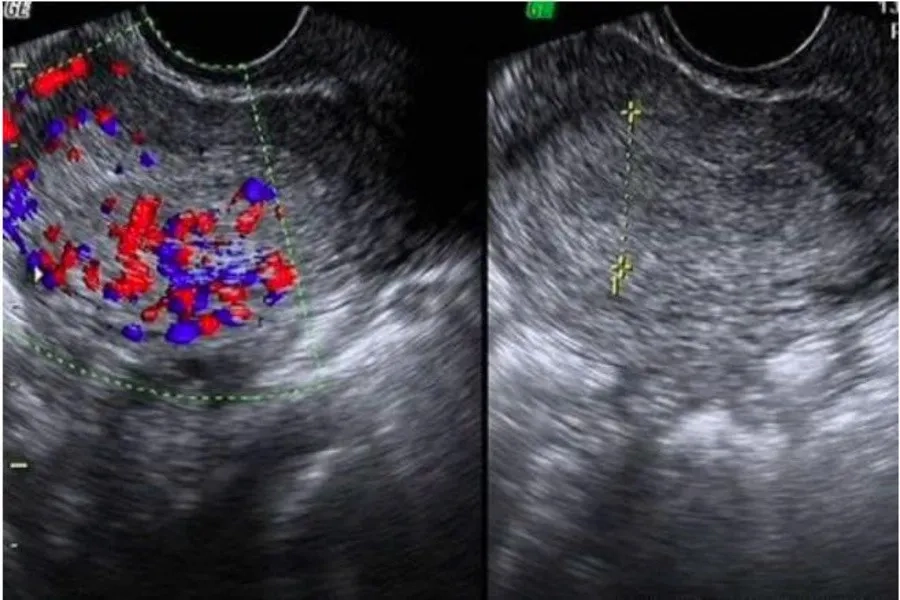

1. Siêu âm đầu dò âm đạo

Đây là phương pháp quan trọng nhất và có độ chính xác cao trong chẩn đoán thai ngoài tử cung.

Siêu âm đầu dò giúp:

- Kiểm tra xem túi thai có nằm trong buồng tử cung hay không.

- Phát hiện khối cạnh tử cung nghi ngờ thai ngoài.

- Đánh giá tình trạng dịch trong ổ bụng (gợi ý vỡ thai, chảy máu ổ bụng).

- Trong giai đoạn rất sớm, túi thai có thể chưa thấy rõ, nên bác sĩ sẽ hẹn theo dõi lại sau vài ngày.

Siêu âm là cách chẩn đoán chính xác thai ngoài tử cung